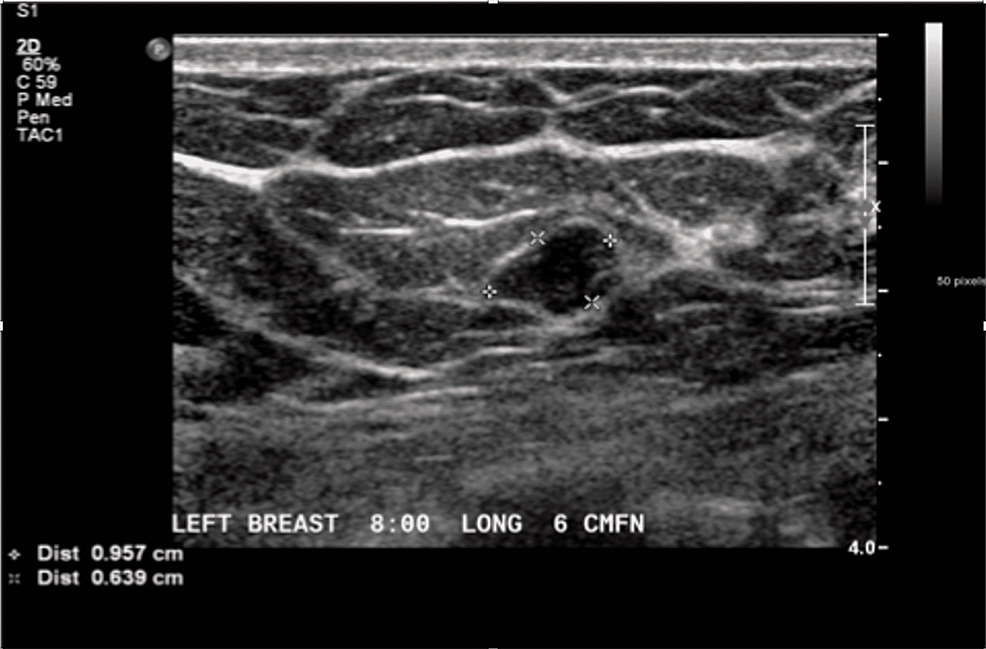

From radiopaedia.org

Phyllodes tumor Image Probe Test Phyllodes The latest world health organization classification of breast tumors recommends diagnosing malignant phyllodes tumors (mpts). Having a benign phyllodes tumor does not affect your breast cancer risk. An incisional biopsy is performed and shows the. How do phyllodes tumors affect your risk for breast cancer? All phyllodes tumors contain a stromal component that can vary significantly in histologic appearance from. Probe Test Phyllodes.

Phyllodes tumor Image Probe Test Phyllodes An incisional biopsy is performed and shows the. How do phyllodes tumors affect your risk for breast cancer? On physical examination, the physician palpates a large, firm, mobile breast mass that is nontender to palpation. Having a benign phyllodes tumor does not affect your breast cancer risk. Cystosarcoma phyllodes is a rare, predominantly benign tumor that occurs almost exclusively in. Probe Test Phyllodes.

Phyllodes tumor Image Probe Test Phyllodes All phyllodes tumors contain a stromal component that can vary significantly in histologic appearance from one lesion to. An incisional biopsy is performed and shows the. Cystosarcoma phyllodes is a rare, predominantly benign tumor that occurs almost exclusively in the female breast. The latest world health organization classification of breast tumors recommends diagnosing malignant phyllodes tumors (mpts). On physical examination,. Probe Test Phyllodes.